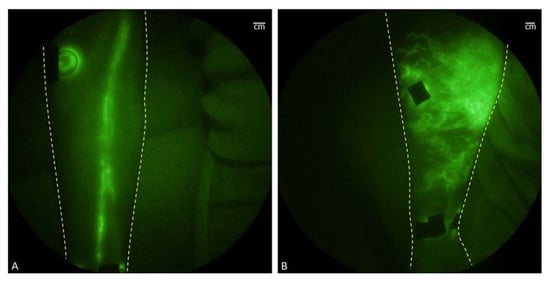

- Hu, Y.; Chi, C.; Wang, L.; Liang, P.; Liu, F.; Shang, W.; Wang, W.; Zhang, F.; Li, S.; Shen, H.; et al. A Comparative Study of Clinical Intervention and Interventional Photothermal Therapy for Pancreatic Cancer. Adv. Mater. 2017, 29, 170048. [Google Scholar] [CrossRef]